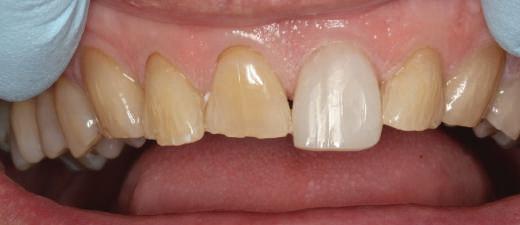

Fig. 1 prezintă pacientul după inserarea primului set de bonturi implantare individualizate; dinţii naturali adiacenţi

sunt încă prezenţi pentru a susţine puntea provizorie.

Cazul (1): Reprepararea intraorală a bonturilor Figurile

1. Aspect după inserarea primului set de bonturi implantare individualizate.